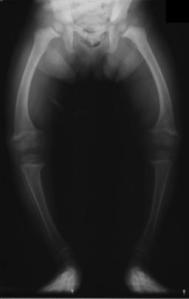

raşitizimD vitamini son 5 yılda oldukça popüler olan bir konu. Öncesindeki popülaritesi çocuklardaydı. Raşitizm benim öğrenciliğimde bile halen görülürken, neyse ki son zamanlarda bu sıklıkla görülmüyor. Fotoğrafta gördüğünüz ise tipik raşitik bir çocuğun O şekline gelmiş bacakları.